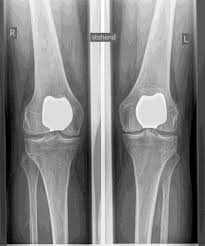

Impaired mobility or instability, as well as the shape of the kneecap (dysplasia), can lead to cartilage damage and osteoarthritis ISOLATED IN the patellofemoral joint. IF THE OTHER COMPARTMENTS ARE FREE OF ARTHROSIS, there is the possibility of an

isolated partial knee replacement of the patellofemoral joint.